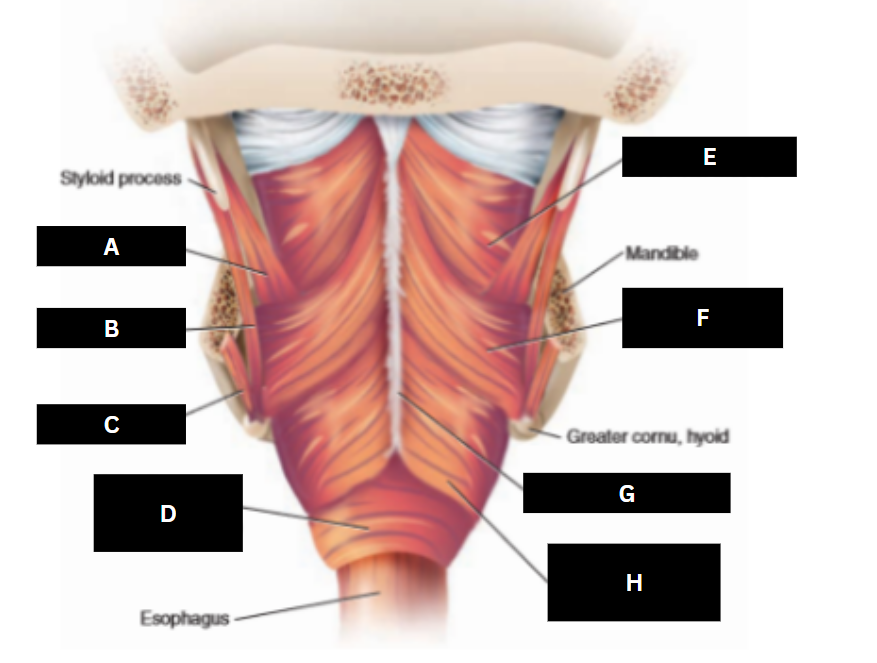

Stylopharyngeus

A

Styloglossus

B

Stylohyoid

C

Cricopharyngeus

D

Superior pharyngeal constrictor

E

Middle pharyngeal constrictor

F

Pharyngeal raphe

G

Inferior pharyngeal constrictor

H